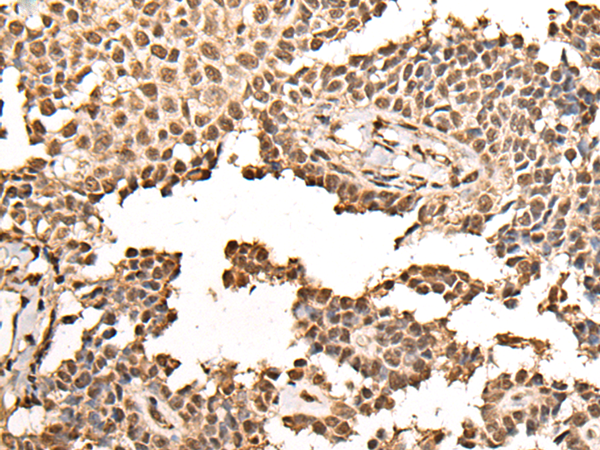

IHC positive control: |

Human ovarian cancer and human thyroid cancer |

ELISA, IHC |